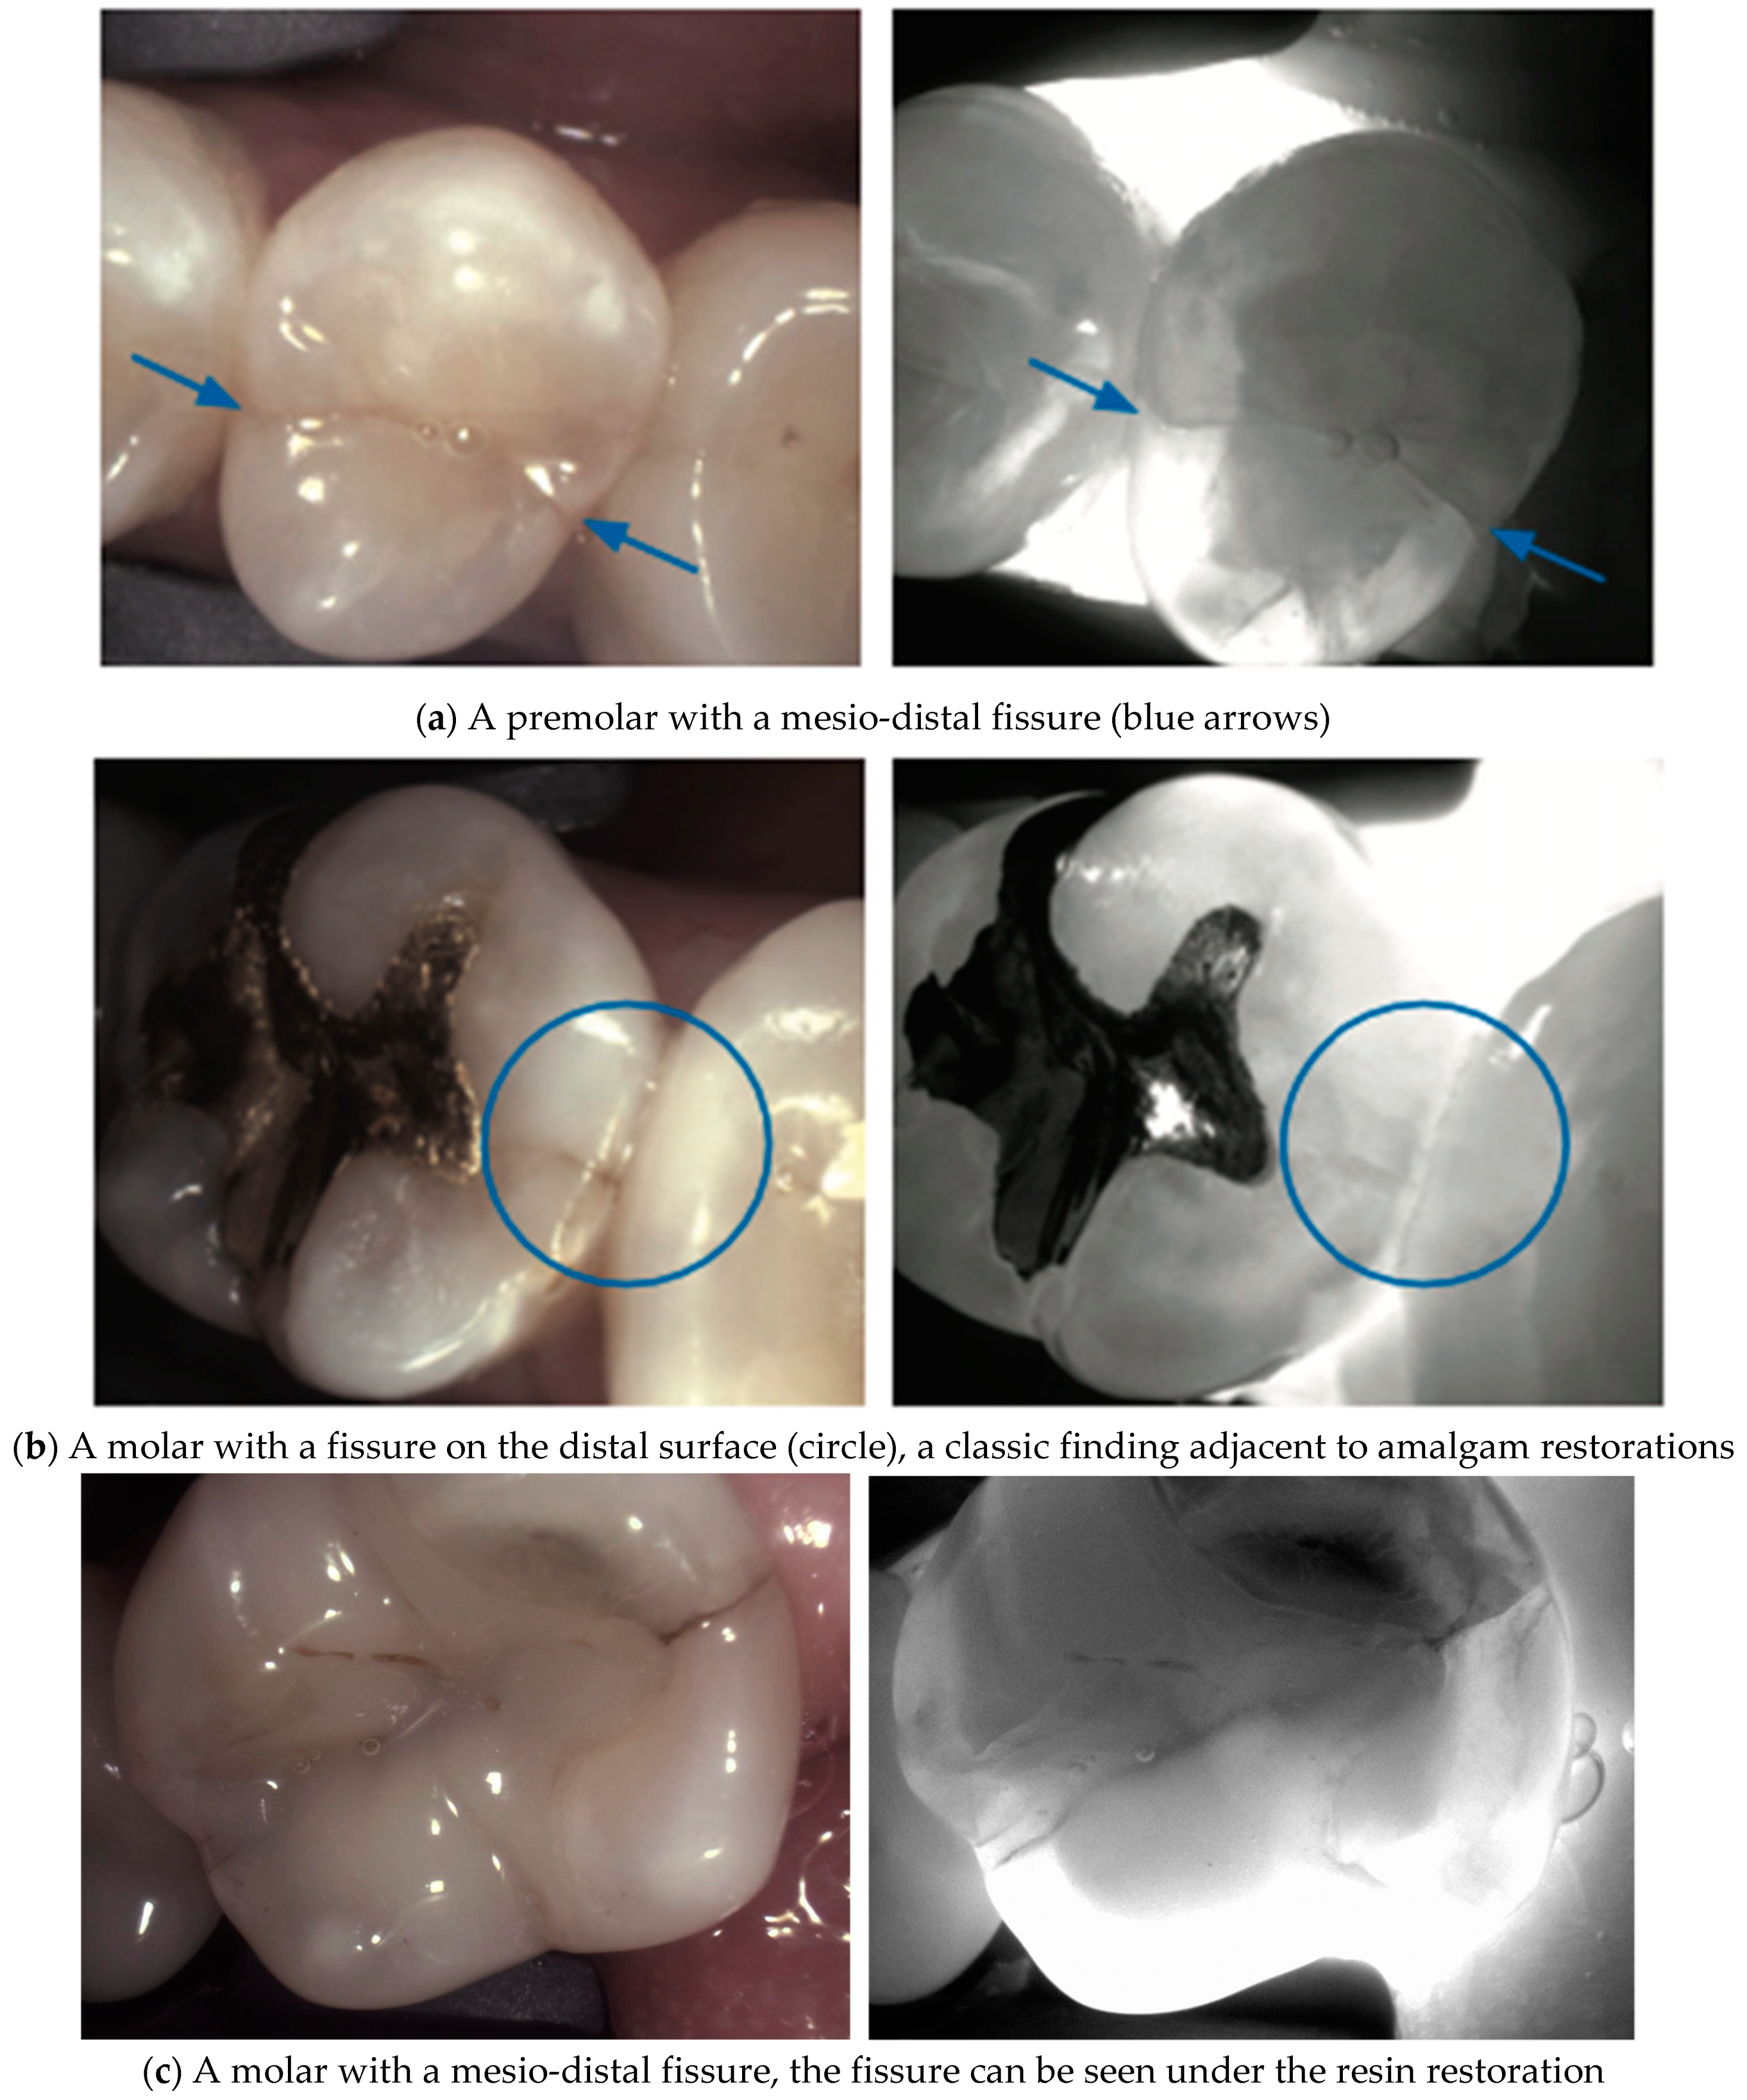

4. Enamel Defects

5. Diverse Findings